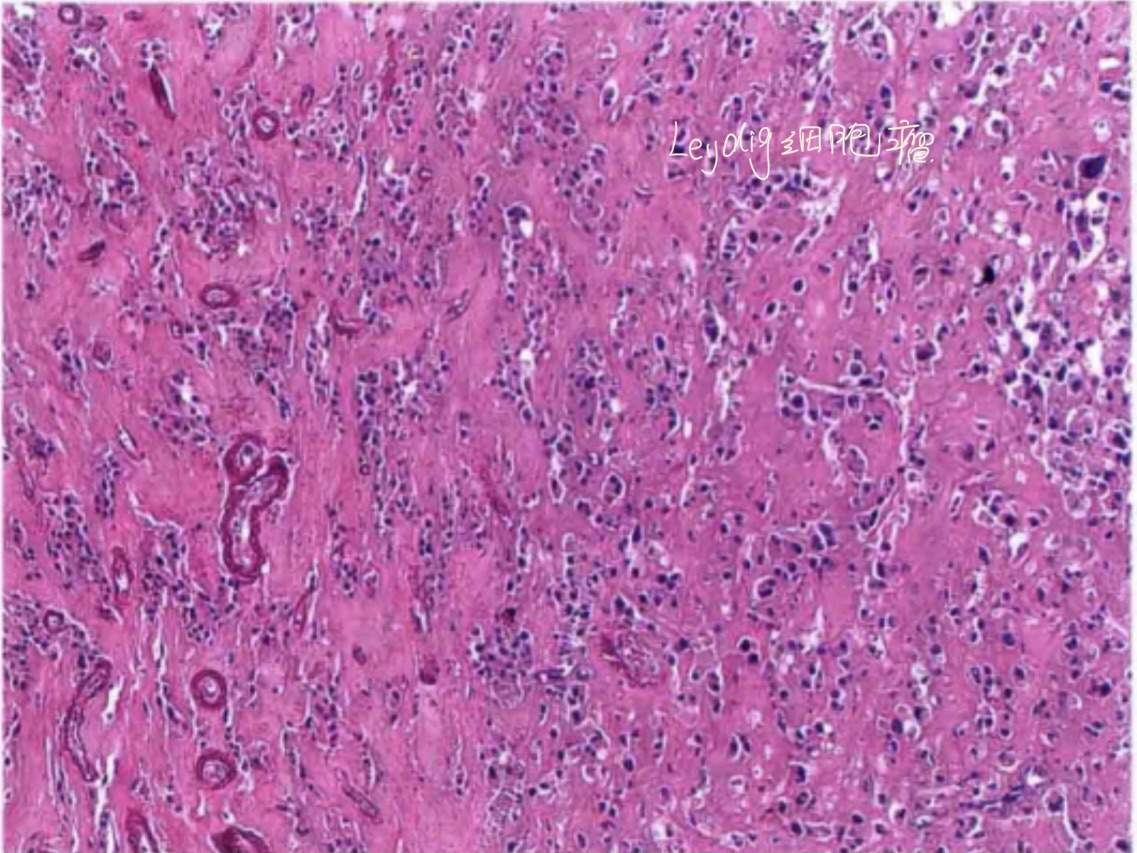

3)Leydig细胞瘤

Reinke结晶是诊断它的铁证,如图:

典型的组织学形态也可以诊断,如图:

当,即没有Reinke结晶,有没有典型的组织学形态时常常被诊断为:类固醇细胞肿瘤。